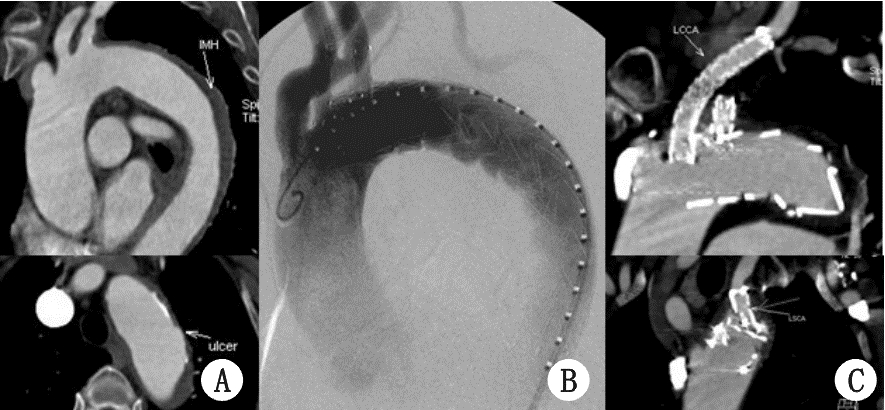

| A:对照组;B:ALI组 图 1 病例1,A:术前CTA可见壁间血肿和穿透性溃疡;B:术中单分支支架和LCCA烟囱支架释放后造影;C:术后6月随访CTA,单分支支架和烟囱支架通畅,无内漏,单分支支架扭曲至LSA开口约40%狭窄 |

所有患者均一期手术成功,支架主体定位精确,烟囱支架位置形态好,术后造影无明显狭窄。未发生死亡、脑梗死、肾功能不全等围手术期严重并发症,术后造影穿透性溃疡封闭良好,夹层近端破口被封堵,未见明显内漏。随访期间,无患者死亡。随访12~18个月,随访CTA显示:支架形态良好,无明显移位,主动脉壁间血肿被吸收,术后6个月随访1例左锁骨下动脉分支支架在左锁骨下动脉开口处狭窄约40%,12个月随访时无明显改变(图 1 C箭头),进一步随访中;其余2例分支支架通畅无狭窄扭曲,3例患者均未见明显内漏(图 1-3 )。1例左颈总烟囱支架术后6个月随访时,被主体支架压迫烟囱支架使颈总开口处狭窄(图 2C,D),术后12个月随访时在颈总动脉开口处血栓形成闭塞(图 2E,F),无头晕、脑梗等颅内缺血表现,未做特殊处理,继续随访中。